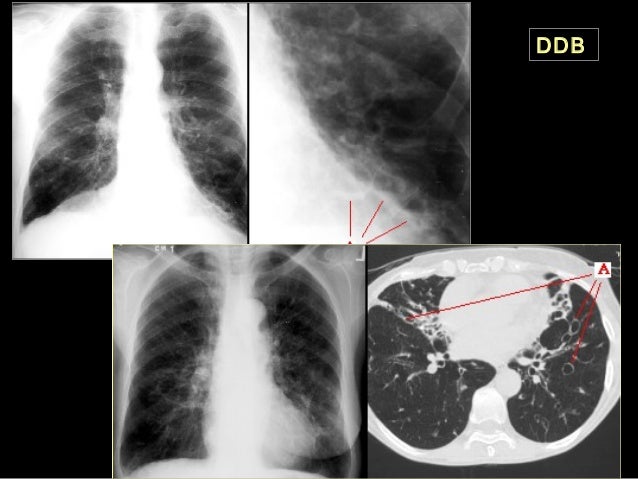

Hernie hiatale RP hernie hiatale La hernie hiatale, béance de l’orifice diaphragmatique laissant passer l’oesophage thoracique dans l’estomac abdominal, est parfois très volumineuse et quand elle se produit par glissement, le haut de l’estomac peut saillir dans le thorax. Le reflux gastroœsophagien peut être provoqué par une hernie hiatale une partie de l'estomac passe dans le thorax, tiré par l'œsophage Du coup le contenu. La hernie hiatale de type 1 ou par glissement qui représente environ 85 à 90% des cas La partie supérieure de l'estomac remonte dans le thorax à travers le hiatus La hernie hiatale de type 2.

Hernie hiatale Thorax de face 1, Poumon droit 2, Trachée 3, Aorte 4, Poumon gauche Masse médiastinale rétrocardiaque avec niveau hydroaérique Les flèches rouges montrent le contour de la masse médiastinale, rétrocardiaque, ronde La flèche jaune pointe sur le niveau hydroaérique. Une préparation et des précautions sont toujours nécessaires pour ce type d’examen Vous devrez donc vous déplacer jusqu’ au Centre de Radiologie 163 avenue d’Alsace à COLMAR muni de votre ordonnance ou du courrier de votre médecin ainsi que de la liste écrite des médicaments que vous prenez.